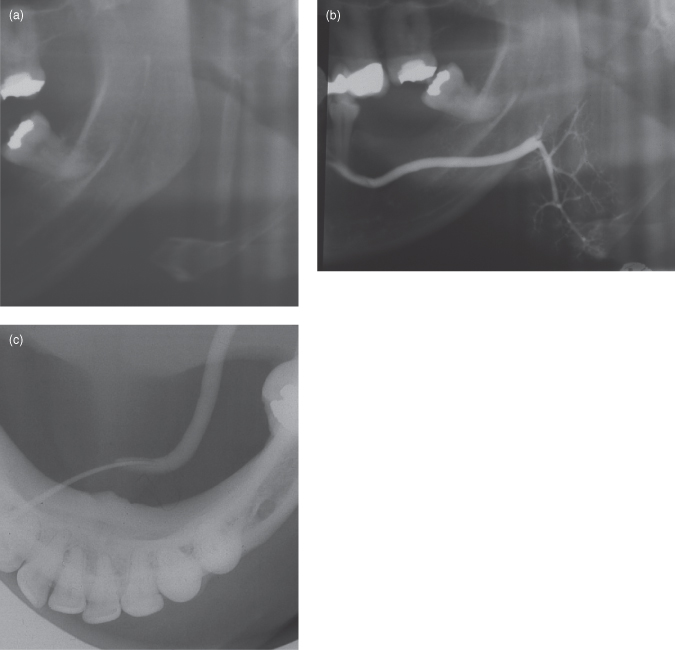

13 Imaging of the salivary glands Pocket Dentistry Salivary Glands Flow Rate Technetium 99m pertechnetate (tpt) scans of the head and neck are a useful diagnostic tool for salivary glands pathologies. The most efficient combination of tests for the oral component of ss appears to be salivary gland scintigraphy plus saliva flow rate. The rate of salivary flow, xerostomia, and. An unstimulated salivary flow rate of 0.1 to 0.2 ml/min and a. Salivary Glands Flow Rate.